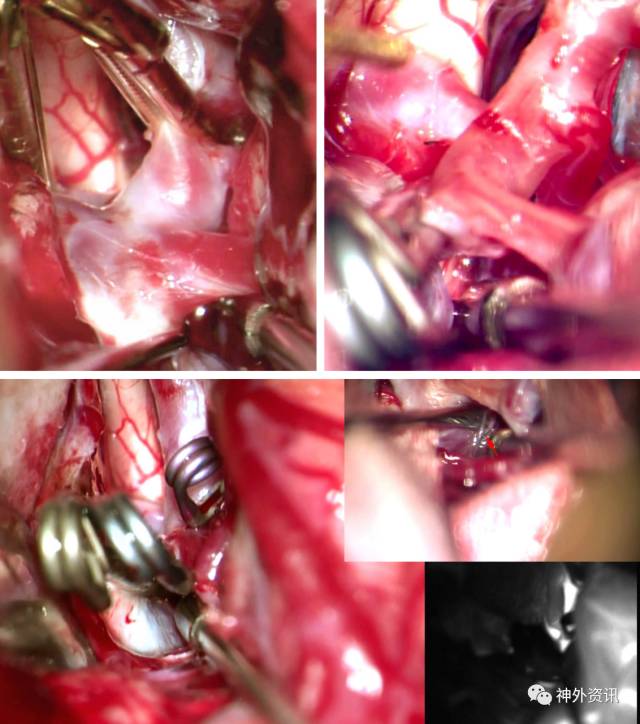

图9:瘤颈后方隐藏有与之黏连的穿支血管、脉络前和Heubner回返动脉,术中经常需要临时阻断近端ICA以便更彻底地松解瘤颈。术者应该轻柔、仔细、全方位地探查这部分瘤颈,确保所有穿支已被解离,避免盲视下置入动脉瘤夹。

最后,靠A1侧的远端瘤颈也被分离出来,术者已可以在瘤颈内外两侧做操作。完全控制从M1延伸至A1的瘤颈全程是实施安全夹闭的有效保障。

图10:宽颈动脉瘤手术中,在穿支血管与瘤颈之间垫入明胶海绵隔离两者,当随后伸进瘤夹的咬合叶片时,夹子尖端往前推移海绵,而不会误伤到后方的小动脉。下文图12将有更详细介绍。

图12:如前述,在穿支血管与瘤颈内侧之间垫入小片明胶海绵隔离两者,当瘤夹的内侧咬合叶片绕过瘤颈时,海绵被前推以保护后方的小穿支。

图13:夹闭完成后行荧光造影明确动脉瘤是否完全闭塞以及载瘤动脉和穿支血管的通畅程度,但是要注意穿支动脉的显影效果本身就不好。之后细针穿刺瘤顶证实动脉瘤血流已被阻断。插图表示使用吸引器清除瘤腔内的血液使瘤壁塌陷。

图14:瘤腔塌陷后再次彻底探查瘤周,必须保证穿支血管通畅。若有瘤颈残余,可以阻断ICA后调整瘤夹。